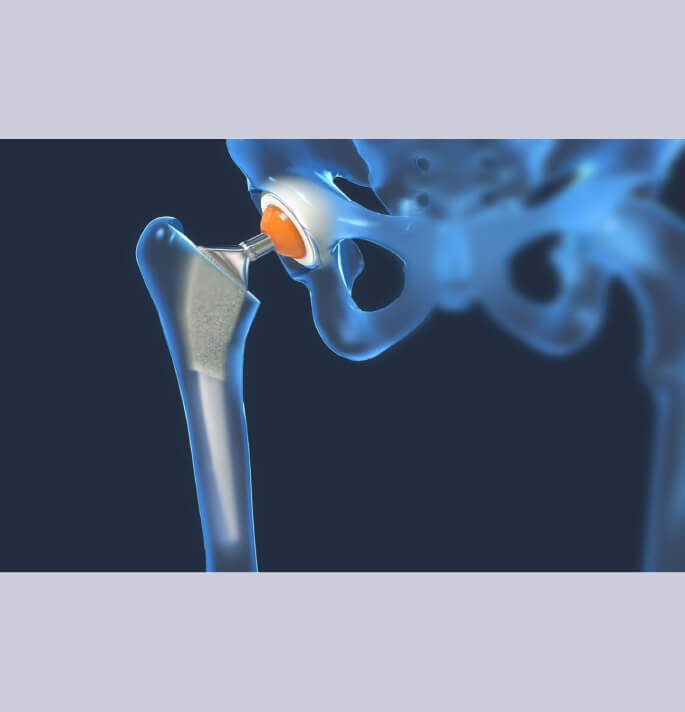

Bij ernstige slijtage van het kraakbeen van de heup bestaat de enige oplossing uit een totale heupartroplastie.

Met de meeste gekende toegangswegen tot de heup zijn de posterieure en anterieure toegangsweg.

De posterieure toegangsweg is de meest versatile toegangsweg pijn door het gebruik van de super path techniek is dit ook een spiersparende chirurgie.

Beenderig wordt de versleten heupkop verwijderd en vervangen door een titanium cup in de heup pan (niet gecementeerde acetabulaire component) en een niet gecementeerde titanium heupsteel welke in het mergkanaal wordt ingebracht. In de metalen cup van het acetabulum wordt een glijlaag (liner) in polyethyleen of ceramiek ingebracht.

Op de femorale component wordt dan een bijpassend kopje in metaal of ceramiek geplaatst.